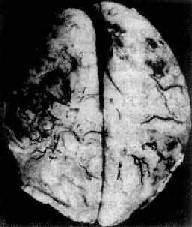

慢性脑脓肿

图16-12 慢性脑脓肿

右侧颞叶的脑脓肿与侧脑室相通